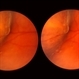

- 28 year old female with sub-ILM hemorrhage and questionable cotton wool spot. Pt states sudden vision loss after being hit in the eye with laser lights at a nightclub. Laser lights also damaged the camera in her iPhone. Will give hemorrhage more time to clear on its own, will discuss treatment options if no improvement at next visit.